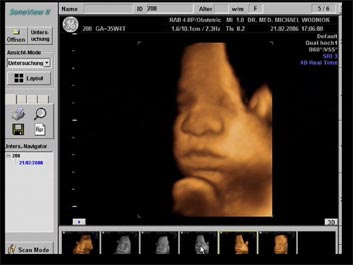

Weitere Ultraschalluntersuchungen sind in der 10./20./30. Schwangerschaftswoche gemäß den Mutterschaftsrichtlinien vorgesehen. Bei erkennbaren Risiken werden  weitere Untersuchungen angeschlossen. Spezielle Ultraschalluntersuchungen zum Ausschluss von kindlichen Entwicklungsstörungen sowie Durchblutungsmessungen der mütterlichen und kindlichen Blutgefäße mittels Farbdopplersonographie gehören zum Leistungsspektrum der Praxis. Auf Wunsch können auch 3D und 4D Untersuchungen angeboten werden.